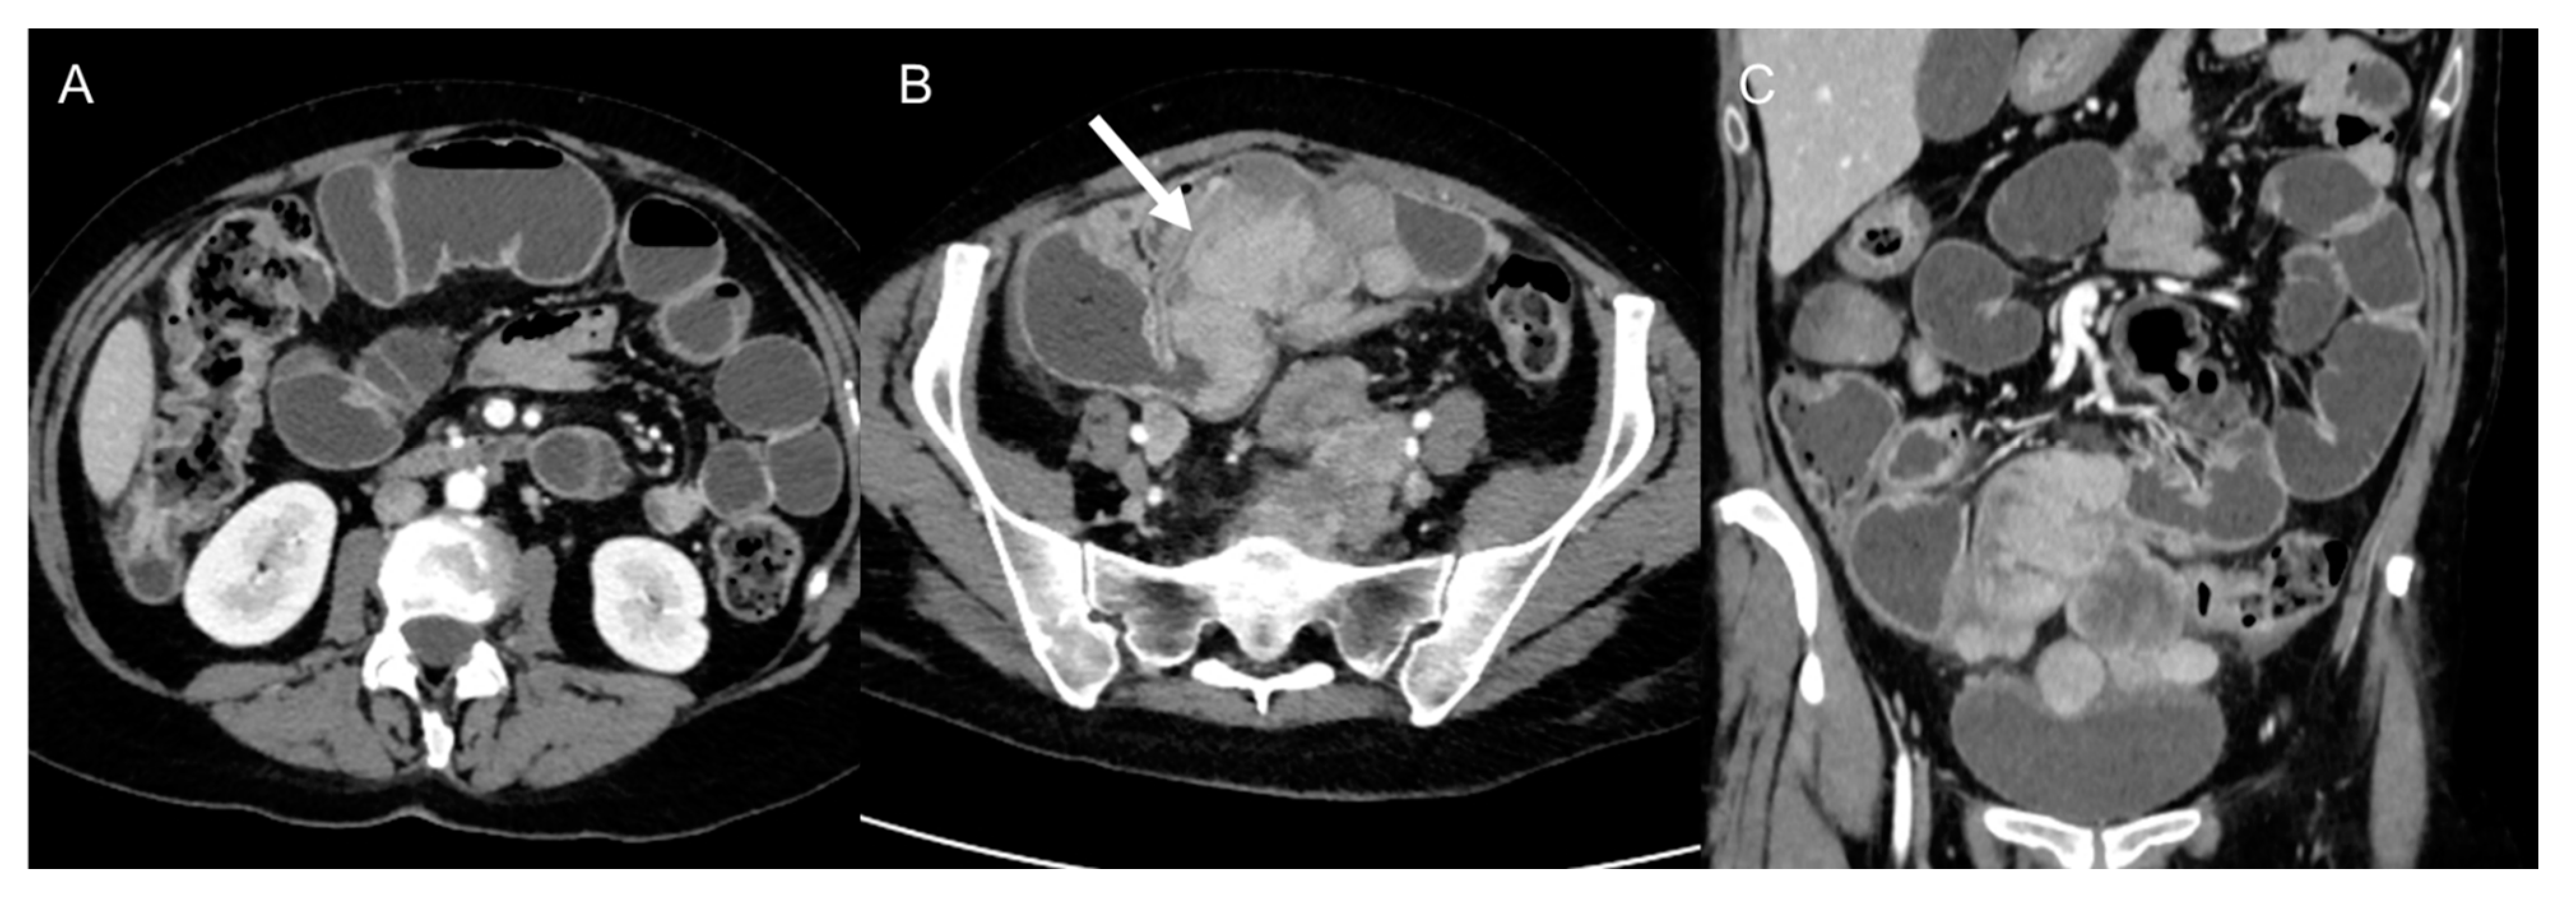

Complications are usually related to tumor invasion of adjacent structures or to mass effect caused by the tumor and include hydronephrosis, pulmonary embolisms secondary to compression of inferior cava vein, nerve compression, bowel obstruction (Figure 11) [49], and even intestinal perforation [50]. Postoperative complications are divided into early and late complications and include pulmonary embolism, ileus, fluid collections, hemorrhage [49], splenic injuries, sepsis, multisystem organ failure. For these reasons, guidelines recommend that immediate postsurgical care should be held in subspecialized facilities [2,19,51,52,53].

Figure 11.

Bowel obstruction in 38-year-old woman with metastatic leiomyosarcoma. Axial (A,B) and coronal (C) CT images on the venous phase show dilatation of small bowel loops with air–fluid levels secondary to the presence of metastatic masses (arrow) in the pelvis.